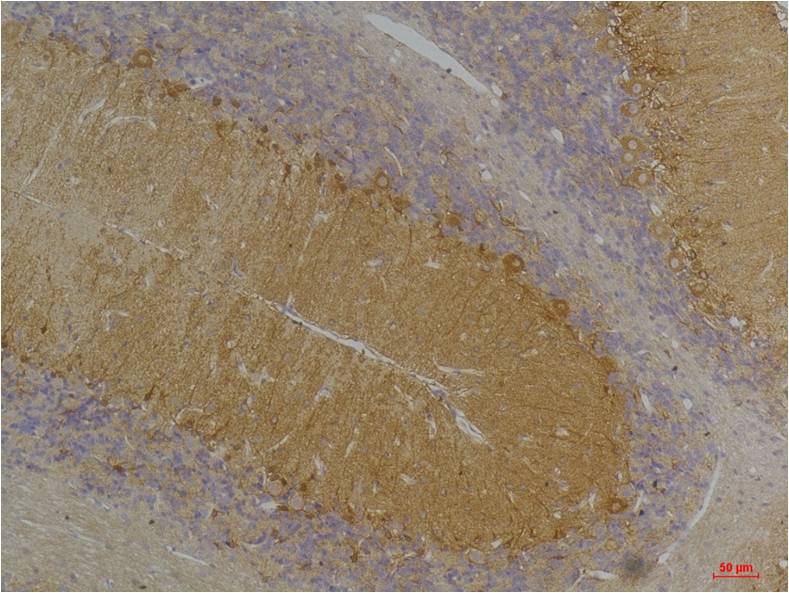

Immunohistochemical analysis of paraffin-embedded Rat BrainTissue using?KCNN3(SK3) (EA301)Rabbit pAb diluted at 1:200.